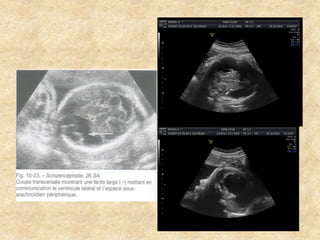

-Aspect des ventricules latéraux

° Taille :Plexus

occupant toute la

largeur de la région de

l’atrium

°Mesure précise du

diamètre

atrial

°Forme des cornes

antérieures

et postérieures

°Aspect des parois

°Contenu